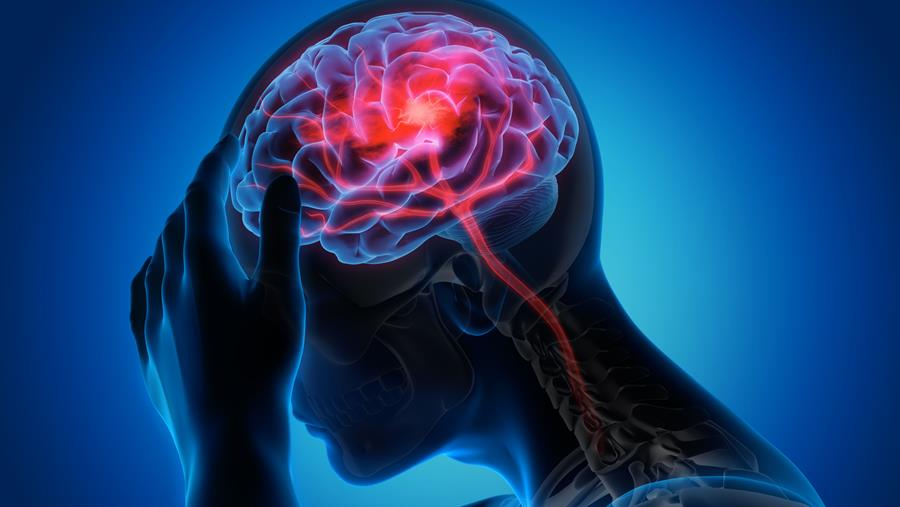

Le Belgian Stroke Council appelle à la mise en œuvre d'un registre national des AVC

Le Belgian Stroke Council (BSC), en collaboration avec l'organisation Testachats, a de nouveau appelé mercredi les autorités belges à mettre en œuvre un plan national pour les accidents vasculaires cérébraux (AVC)